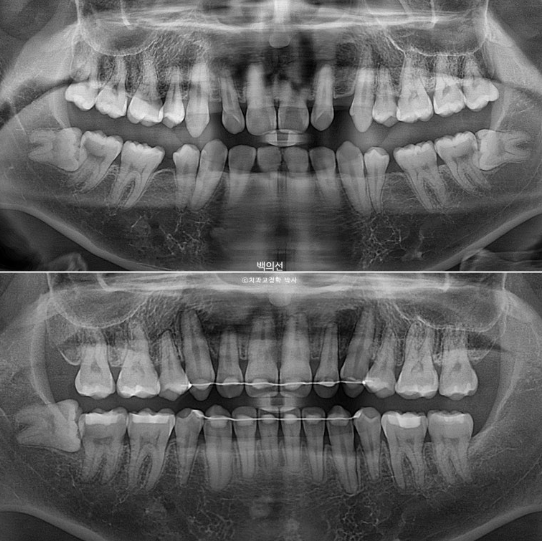

23.07~25.05

초진에 비해 치근흡수는 없고 치근평행도도 좋습니다.